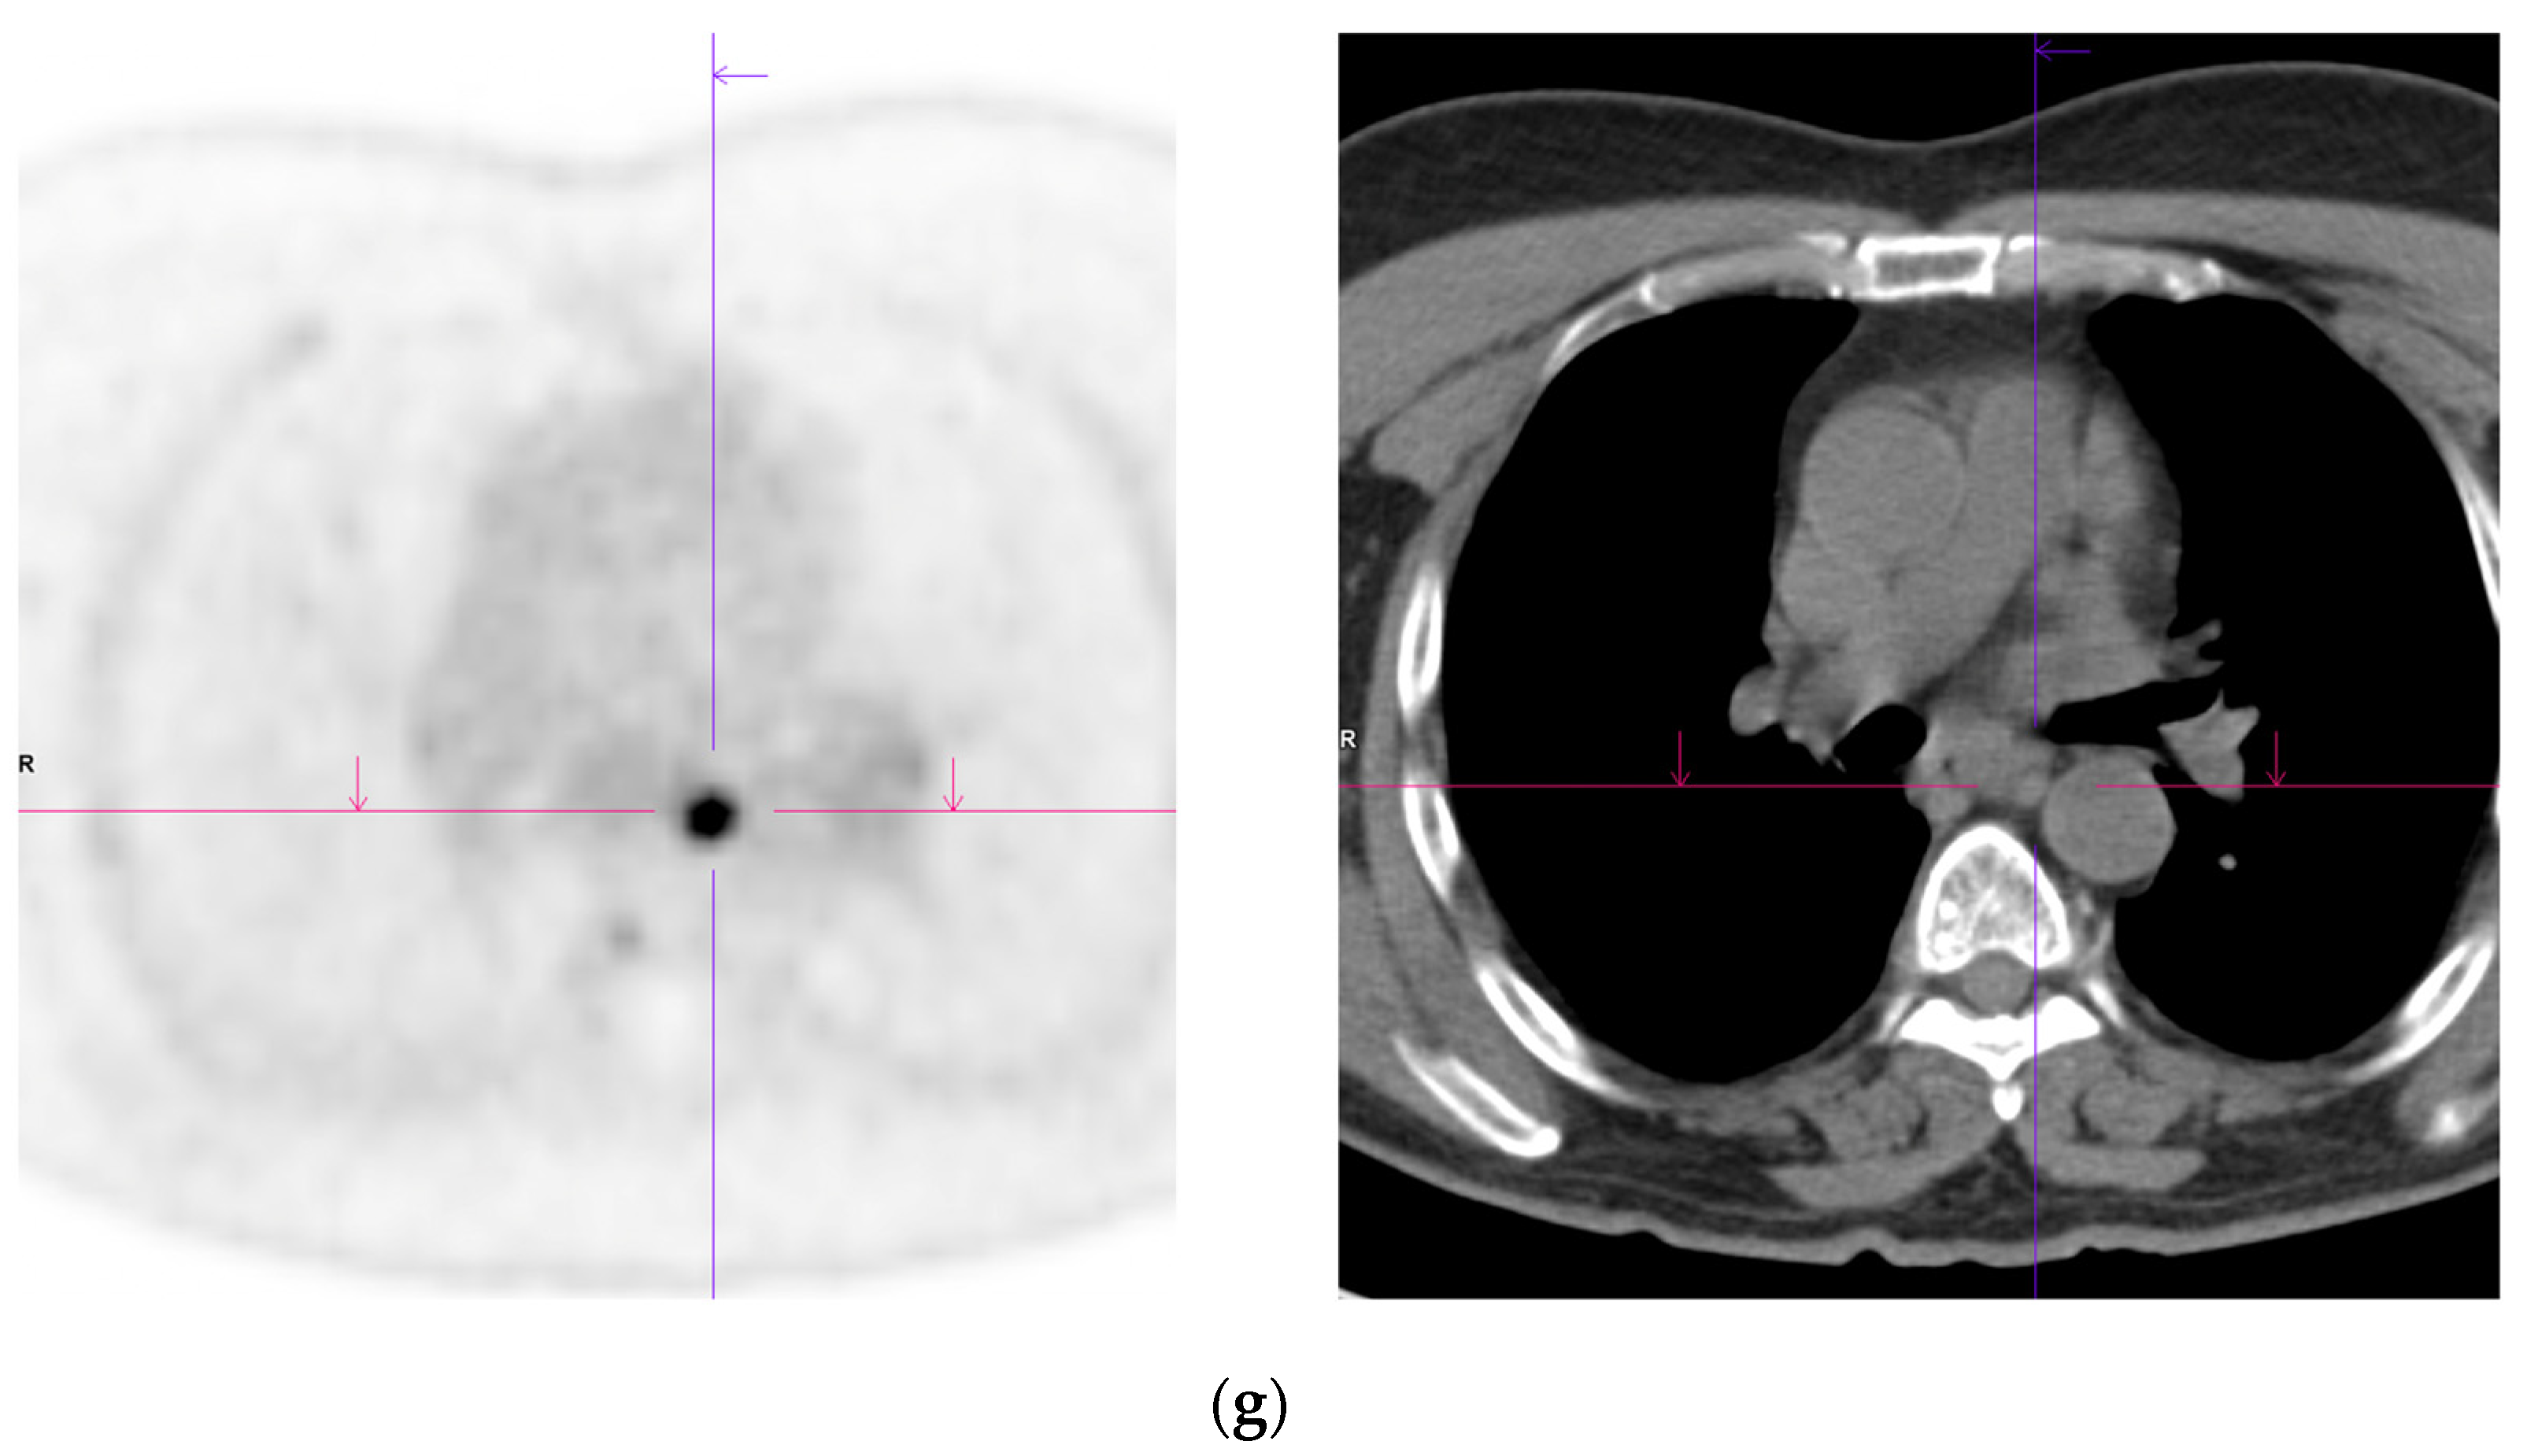

- Damjanovic, J.; Janssen, J.C.; Furth, C.; Diederichs, G.; Walter, T.; Amthauer, H.; Makowski, M.R. 68Ga-PSMA-PET/CT for the evaluation of pulmonary metastases and opacities in patients with prostate cancer. Cancer Imaging 2018, 18, 20. [Google Scholar] [CrossRef]

- Pyka, T.; Weirich, G.; Einspieler, I.; Maurer, T.; Theisen, J.; Hatzichristodoulou, G.; Schwamborn, K.; Schwaiger, M.; Eiber, M. 68Ga-PSMA-HBED-CC PET for Differential Diagnosis of Suggestive Lung Lesions in Patients with Prostate Cancer. J. Nucl. Med. 2016, 57, 367–371. [Google Scholar] [CrossRef]

- Bouchelouche, K.; Vendelbo, M.H. Pulmonary Opacities and Bronchiectasis Avid on 68Ga-PSMA PET. Clin. Nucl. Med. 2017, 42, e216–e217. [Google Scholar] [CrossRef]

- Ardies, P.J.; Gykiere, P.; Goethals, L.; De Mey, J.; De Geeter, F.; Everaert, H. PSMA Uptake in Mediastinal Sarcoidosis. Clin. Nucl. Med. 2017, 42, 303–305. [Google Scholar] [CrossRef] [PubMed]